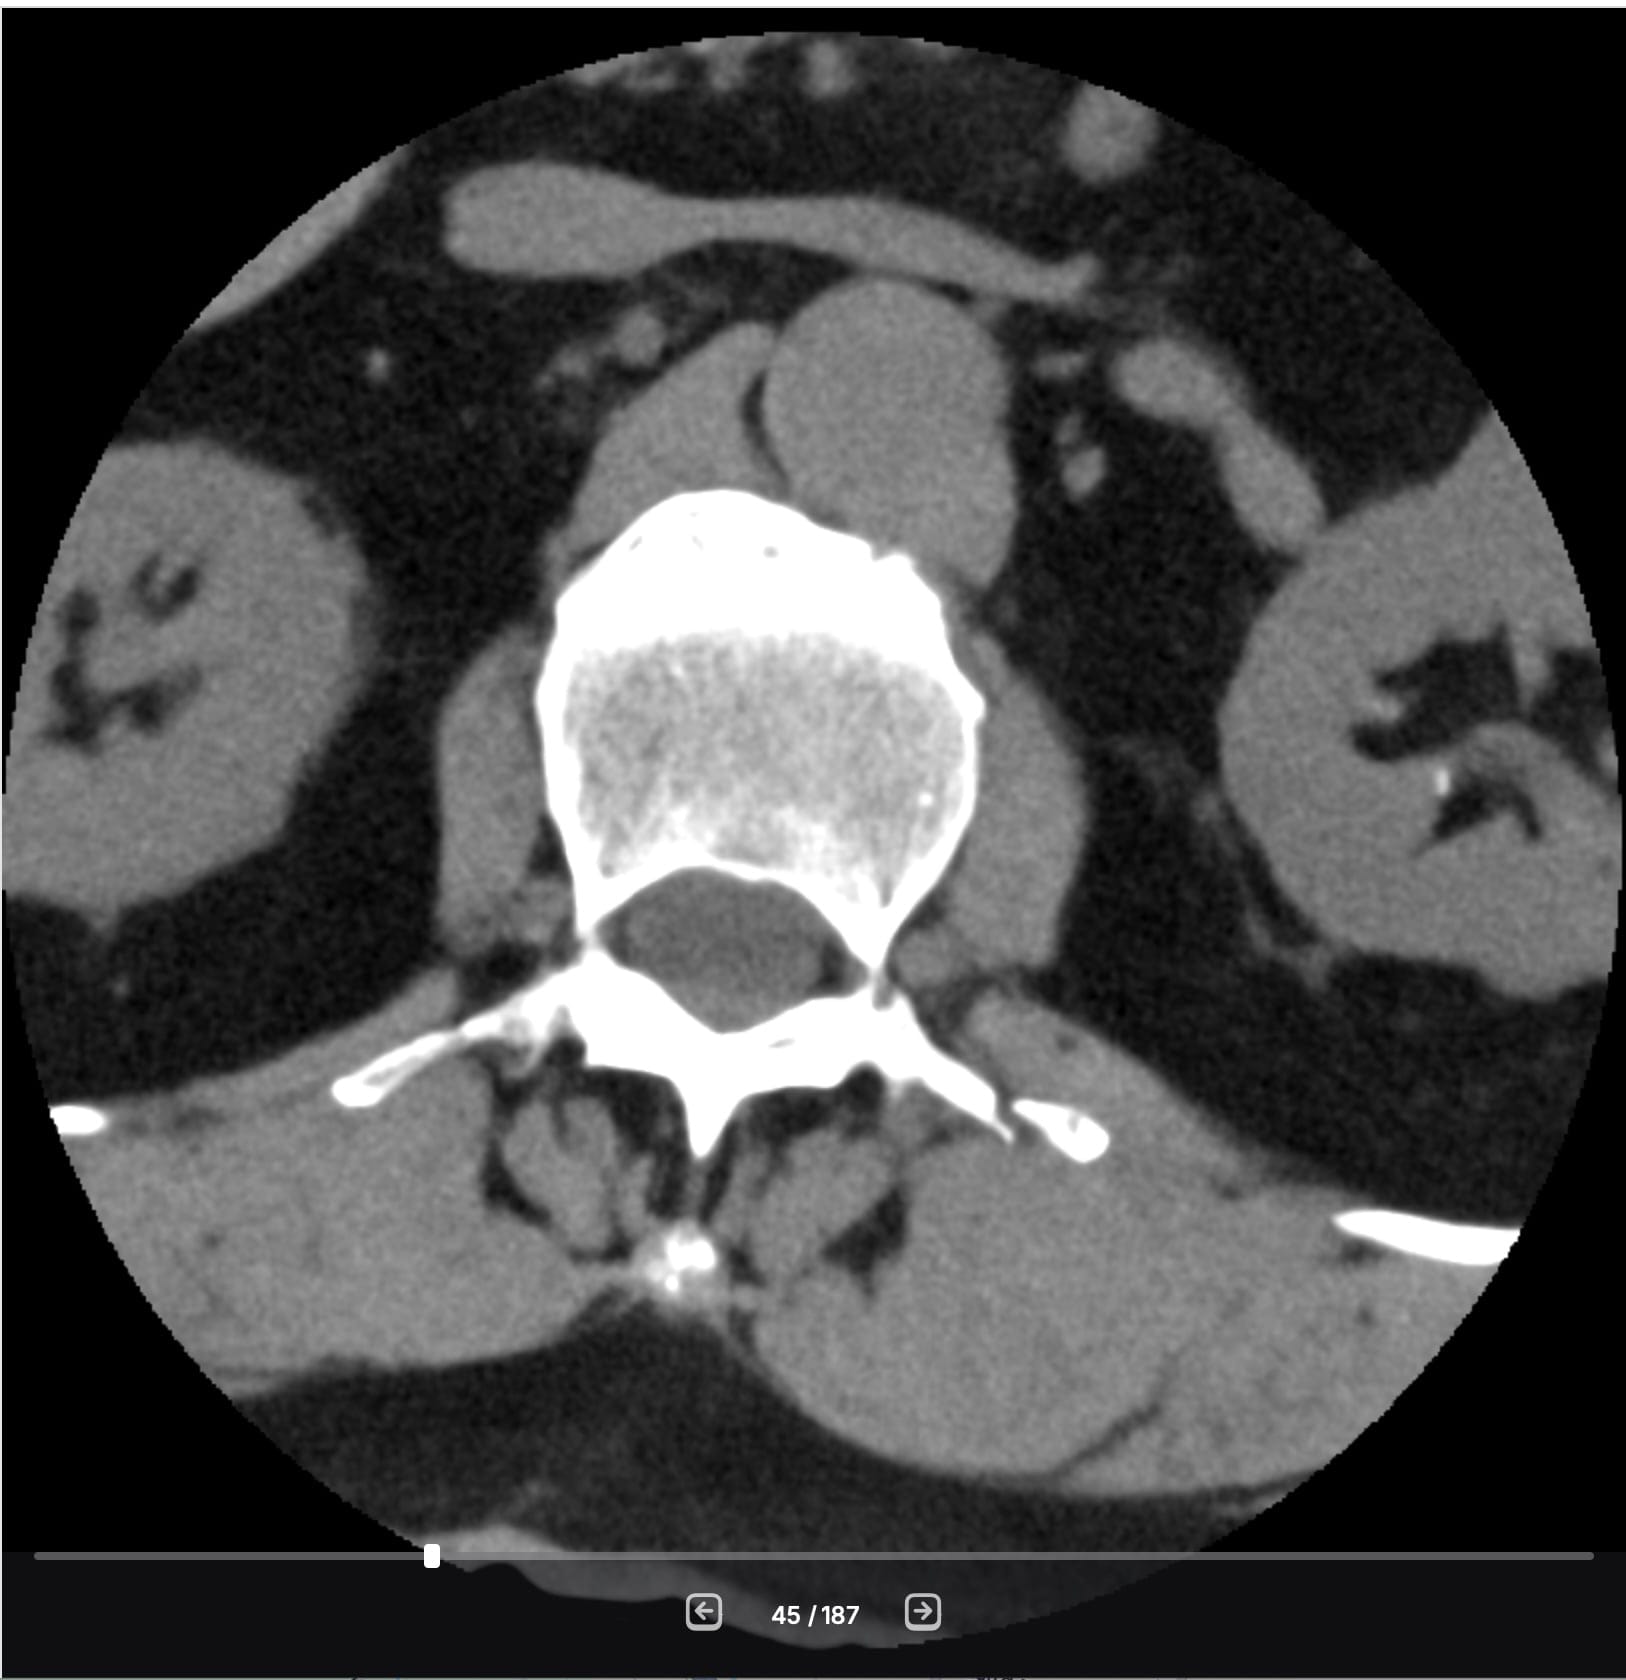

Because this is what you need to do when you have 'minor fractures' of the transverse processes on your spine, as can be seen in my CT scan after my incident in November.

Those three small fractures in my L1-L3 vertebrae don't care about my great VO2 Max. They don't care that I lifted a quarter-million pounds with my back muscles last year. They don't care that I spent a whopping 729 workouts last year, a combination of actual fitness routines, walking, and skiing.

But if I listen to the engine, I destroy the chassis. That's my back. Those 3 small vertebrae are healing. They're still pretty fragile - I'm told I've got another 3 to 5 weeks to go before they have fully fused and are back to 'normal.'